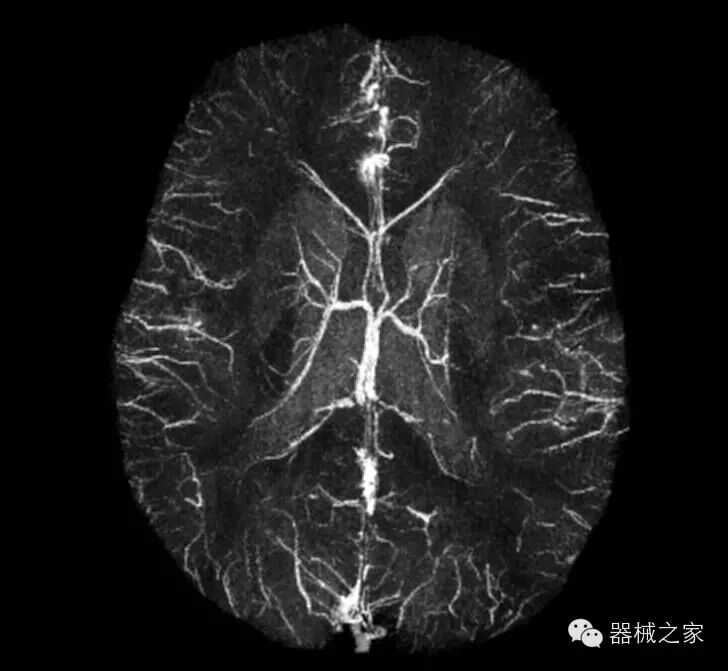

脑部血管

产品特点

·国内首家光纤超导,高品质助力清晰诊断。;

·采用世界先进的数字光纤传输技术和8-32通道并行采集技术,保证精准快速的图像信息;